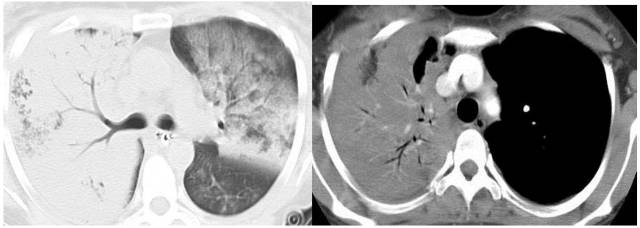

卡氏肺囊虫肺炎:免疫力低+磨玻璃影+实变+间质增生+上肺囊状改变 医学百科网 | YxBaike.Com

巨细胞病毒CMV:多发微结节+磨玻璃影+实变+小叶间隔增厚+纤维化+空气潴留 医学百科网 | YxBaike.Com